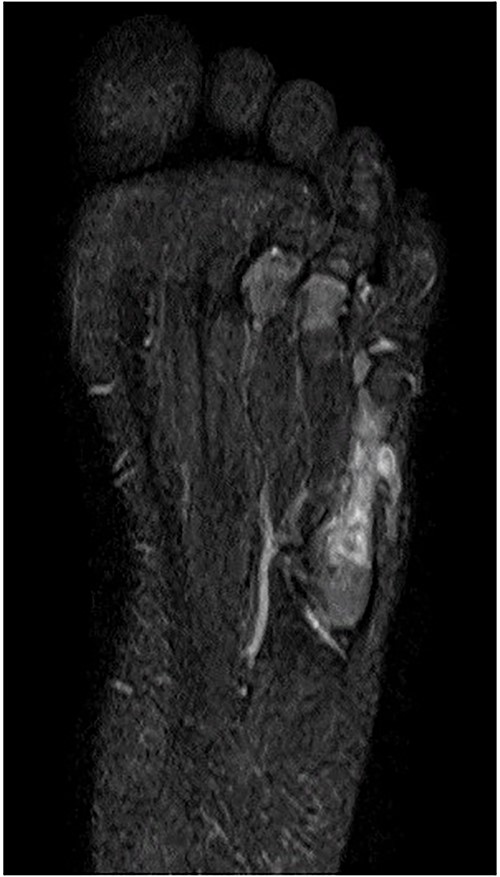

A 21-month-old Japanese female infant presented with a swollen mass on the dorsolateral aspect of the left foot. Her parents noticed the mass and brought the patient to our hospital. The patient had no past medical histories or complications prior to the occurrence. In addition, she received the BCG vaccine at the age of 4 months in Japan. At first visit to our hospital, physical examination revealed the ~3 × 3 cm mass was located on the dorsolateral aspect of the left foot and was hard accompanied by local heat (Fig. 1). Plain radiographs of the left foot showed a lytic lesion without periosteal reaction in the fifth metatarsal bone (Fig. 2). Magnetic resonance imaging (MRI) showed an isointense lesion on T1-weighted images and a hyperintense lesion on T2-weighted images around and within fifth metatarsal (Fig. 3). Gallium scintigraphy revealed intense uptake in the patient’s left foot (Fig. 4). In addition, laboratory examination was within normal. Based on medical history, clinical and imaging findings, we considered the possibility of neoplasia or osteomyelitis and performed an open debridement and biopsy of the lesion to make a diagnosis. The lesion was yellow and consisted of weak, adipose-like tissue that surrounded and continued into the inferior of the fifth metatarsal bone (Fig. 5). The lesion inside and outside the bone was resected as much as possible. Histopathologic examination of the lesion showed granulomatous inflammation including anaplastic giant cells, Langerhans-type giant cells and caseous necrosis (Fig. 6). Based on these results, TB or BCG osteomyelitis was considered as a diagnosis. The tuberculin test was positive, but the QuantiFERON TB test was negative. In addition, samples analyzed using polymerase chain reaction did not identify M. tuberculosis, but did identify the BCG Tokyo-172 strain. Per these findings, the patient was diagnosed with BCG osteomyelitis of the fifth metatarsal and oral treatment with anti-TB medicine including isoniazid (100 mg/day) and rifampicin (150 mg/day) was started. Clinical findings included reduction in swelling of the mass and gradual remodeling of the lytic lesion of the fifth metatarsal on plain radiographs (Fig. 7). However, 10 months after starting the anti-TB treatment, the mass recurred, and MRI revealed a residual high-intensity lesion around and inside the fifth metatarsal on T2-weighted fat-suppressed images (Fig. 8). It was determined that the lesion was difficult to control with anti-TB treatment alone, so an open debridement for the lesion was performed again. Histopathologic examination of the lesion revealed an epithelioid granuloma with necrosis. Therefore, the anti-TB treatment was continued. Six months after the second surgery, clinical and radiographic image findings showed complete improvement (Fig. 9). As a result, anti-TB treatment was ended. At the time of writing this report, 8 years after starting anti-TB treatment, there has been no recurrence.

MRI revealed that a high-intensity lesion remained around and inside the fifth metatarsal on T2-weighted fat-suppressed images.